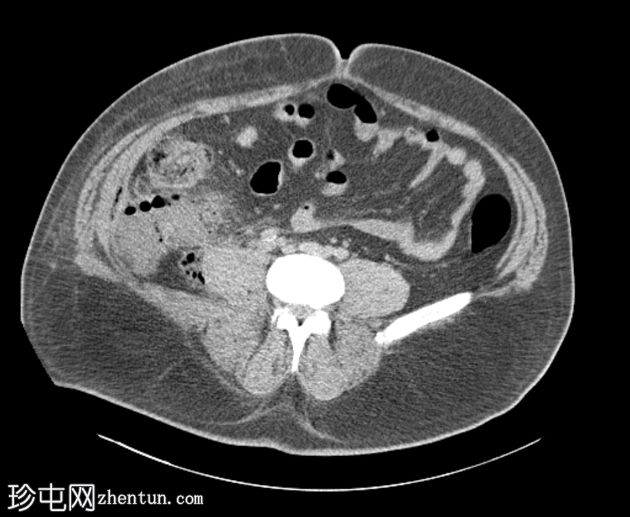

轴位

非增强扫描

可见阑尾后方炎症,阑尾尖端积液,肾后间隙可见大量气体,炎症延伸至肝周、腰大肌后方及腹壁筋膜平面,符合阑尾穿孔引起的广泛性坏死性筋膜炎的

影像

学表现。

病例讨论

阑尾穿孔是坏死性筋膜炎的

罕见病

因。本病例经手术证实,已行阑尾切除术及受累区域清创术。